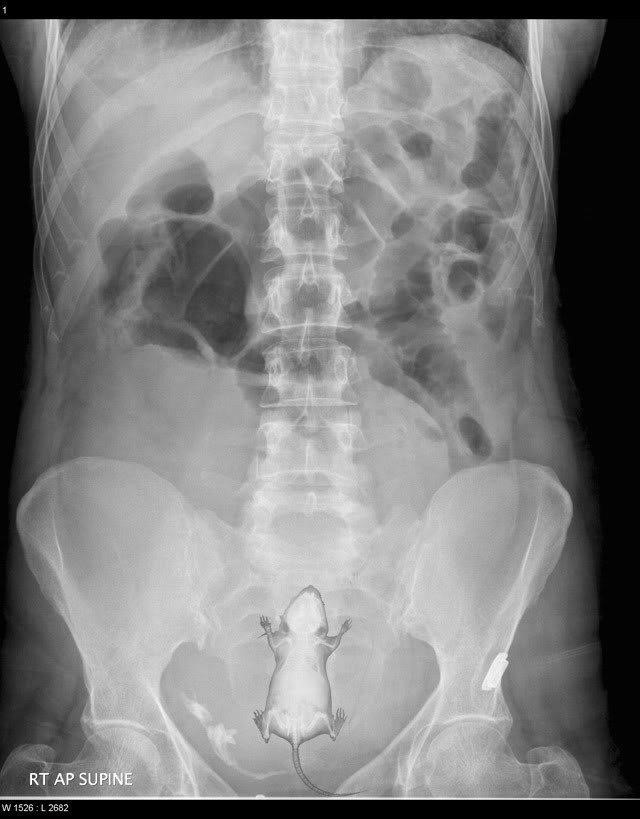

??? : 누나 뷰지에 햄스터 들어감 ㅋㅋㅋㅋㅋㅋ

뷰지에 햄스터박힌 엑스레이